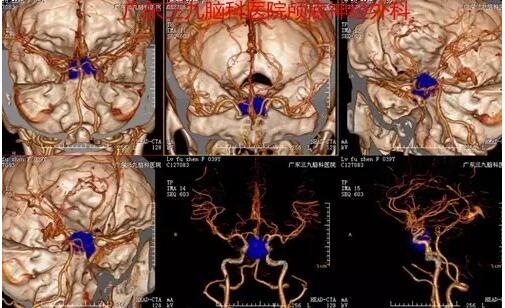

图3:术前CTA提示肿瘤血供丰富,病变紧贴双侧颈内动脉虹吸段